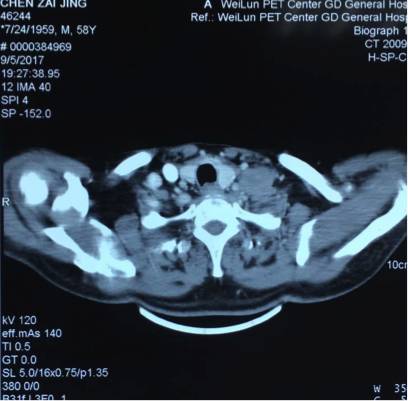

5. 2017-9-5广东省人民医院PET提示:右肺下叶肿物2.8*2.7cm,SUV 22.3,双侧颈部、双侧气管旁、隆突下、食管旁、右侧肺门淋巴结肿大,代谢升高,考虑为转移灶,右侧肾上腺转移灶,具体结果见下图:

吴一龙医生这个病例的PET-CT有一个特点,右肺下叶的病灶并不大,2.7*2.8cm,但是代谢非常高,高达22.3。这种小病灶高代谢的病灶,在肺癌患者中比较少见。尤其是代谢值大于20但病灶小的情况很少见。我同意谢主任刚的意见,如果该患者没有肾上腺的病灶,我认为诊断可以到此为止。我们可以看到,肺内的病灶有可能是肺内的淋巴结,我们已经对最大的淋巴结进行了活检,为良性病灶。但是,由于该患者多了肾上腺的病灶,用刚才的说法无法解释,肾上腺不属于淋巴系统。结合既往我们遇到的病例,我们现在有两个办法,我认为对于该患者,观察是一个办法,但是如果漏诊会比较麻烦,如果观察一段时间,下次过来复查提示病灶稍增大,我们如何处理?因此我认为现在我们要明确诊断,需要取病理活检,但是是取肺部病灶还是肾上腺的病灶?